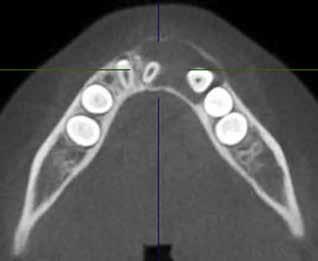

overbid (VOB). Papillen mellem 1+1 er betydeligt reduceret pga. fæstetab, og de mesialt kippede 1+1 har resulteret i en ”dark triangle”. Den facioorale funktion er for nuværende i.a. Panoramarøntgen (Fig. 1, I) viser marginalt knogletab i begge kæber og fravær af 8,7+7,8 og 8,7-8.

Objektivt anbefales behandling af det dybe bid, som ubehandlet forventes at forværres yderligere over tid. Patienten har ønske om behandling med æstetisk ortodontisk apparatur, alignere, og det vurderes muligt at behandle malokklusionen med alignere. Dog anbefales det generelt, at alignere undgås eller benyttes med væsentlige modifikationer af alignerens retention ved tandmobilitet, da dette ellers kan medføre jiggling, når aligneren tages af og på mange gange dagligt. På den anden side er der nogen evidens for, at alignerbehandling er associeret med bedre renhold og parodontal sundhed sammenlignet med fast apparatur (16).

Der planlægges alignerbehandling af begge kæber med intrusion af 1+1 og 2,1-1,2, nivellering af trangstilling UK med interproksimal reduktion (IPR) (Fig. 2 A, B) og senere IPR OK for reduktion af dark triangles mellem incisiverne efter nivellering. Patienten instrueres i at benytte alignere 20-22 timer/ dag med alignerskift hver 7. dag, og patienten ses hver 3.-8. uge under forløbet. Den første alignerserie består af 16 alignere for nivellering OK/UK og IPR i UK (Fig. 2). Efter denne serie planlægges IPR mellem incisiverne i OK for reduktion af dark triangles (Fig. 3) samt yderligere intrusion af OK og UK-fronten i 12 refinement-alignere. Patienten udviser god kooperation og er meget tilfreds med alignerapparaturet, som er mindre synligt end det faste apparatur (Fig. 4).

Behandlingen afsluttes med yderligere refinement-alignere for finindstilling af okklusionen, og efter 11 måneders ortodontisk behandling er der opnået normale relationer i alle tre